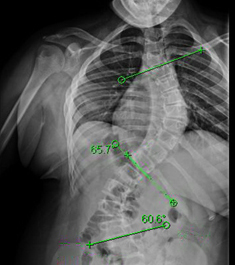

يعاني بعض المراهقين من انحناء العمود الفقري المعروف بالجنف، وخاصة الانحناءات الكبيرة التي تتجاوز 35 درجة. في هذه الحالات، يلجأ الأطباء غالبًا إلى الحزام الطبي (Brace) لتقويم العمود الفقري ومنع تفاقم الانحناء. لكن الكثير من الأهالي يتساءلون: ما العوامل التي تحدد نجاح الحزام؟ وهل يمكن الاعتماد عليه بدلاً من الجراحة؟

الأبحاث أظهرت أن المراهقين الذين لديهم انحناء مزدوج في العمود الفقري أو الذين يكون لديهم زاوية معينة في منطقة الحوض والخصر هم أكثر عرضة لتفاقم الانحناء بالرغم من ارتداء الحزام. هذا يعني أن بعض الحالات تحتاج متابعة دقيقة، وربما تدخل جراحي إذا استمر الانحناء في الزيادة.

المراهقين الذين لديهم انحناء مزدوج (الجزء العلوي والجزء السفلي من العمود الفقري منحني) يحتاجون إلى مراقبة أكبر، لأن هذا النوع أكثر صعوبة في التحكم بالحزام مقارنة بالانحناءات الأحادية.

مدى تقويم الانحناء بالحزام

عند ارتداء الحزام لأول مرة، يقيس الطبيب مدى تصحيح الانحناء بشكل مؤقت. كلما كان الحزام قادرًا على تصحيح الانحناء بنسبة لا تقل عن 25٪، زادت فرصة نجاح العلاج.مدة ارتداء الحزام يوميًا